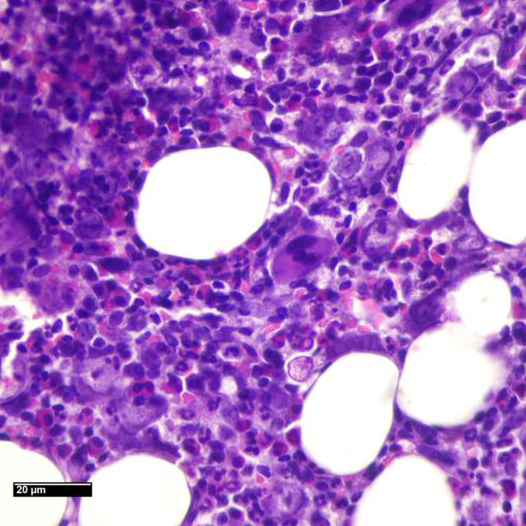

Se realiza punción de médula ósea.

Imágenes Microscopio

C- Cambios citopáticos atribuibles a agente etiológico viral. Sugiero inmunohistoquímica y/o estudio más específico.

Histoquímica: Giemsa

MÉDULA ÓSEA HIPERCELULAR CON CAMBIOS CITOPÁTICOS COMPATIBLES CON INFECCIÓN POR PARVOVIRUS

• La morfología típica muestra una médula ósea hipocelular, no como en este caso; pero las características citológicas de los eritroblastos, resaltadas en la coloración de Giemsa, que muestran macrocariosis e inclusiones nucleares; apoyadas por los hallazgos de la PCR confirman el diagnóstico.